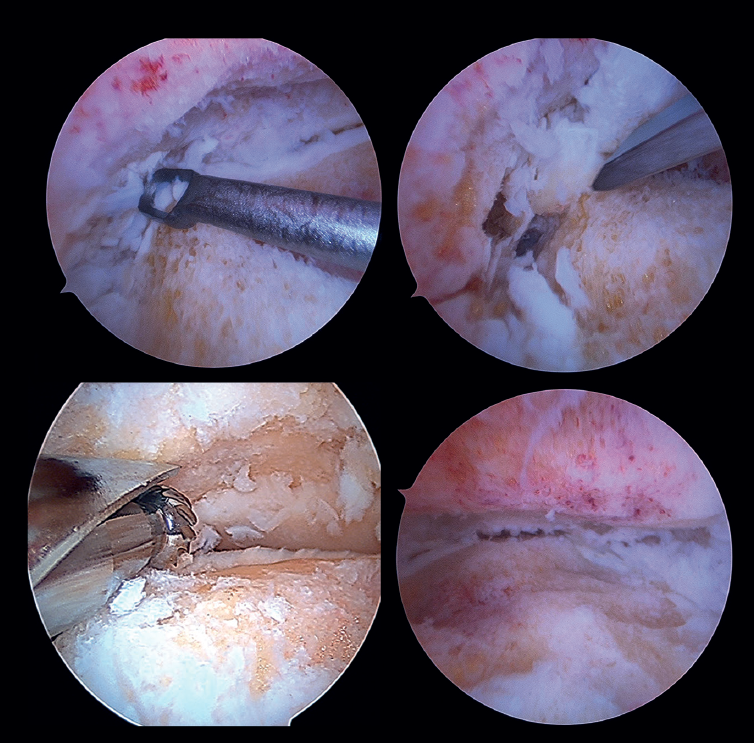

Preparación de superficies articulares (Figura 4)

- En caso de artrofibrosis o sinovitis significativa, se realiza un desbridamiento inicial con un sinoviotomo que permita la visualización de la articulación.

- Pueden presentarse osteofitos anteriores grandes, para cuya resección inicial sea necesario el uso de fresa, cureta u osteotomo, con cuidado de no dañar las estructuras neurovasculares anteriores. Resecarlos de entrada permite, en ocasiones, mejorar la dorsiflexión del astrágalo y una mejor posición neutra en el plano sagital, así como una mejor visualización del campo de trabajo.

Es útil el intercambio de portales de visión y trabajo para acceder a toda la extensión de las superficies condrales y comprobar la resección completa.

El vaporizador es útil en casos de pinzamiento grave y fibrótico, característico de casos postraumáticos o reintervenciones, pero de nuevo debe ser lo más próximo a hueso o espacio articular, para evitar lesiones tisulares anteriores. - No suele ser necesario usar un dispositivo de distracción para abrir la articulación, ya que el espacio articular aumentará progresivamente a medida que se resequen los remanentes de cartílago articular.

- Se procede a la cruentación quirúrgica, la delaminación condral y la exéresis del tejido cartilaginoso hasta obtener un lecho de hueso esponjoso viable. Puede realizarse con o sin apoyo de fresas motorizadas, en función de cada caso.

- Para la preparación de los recesos, se pueden utilizar portales accesorios medial y lateral para el fresado o curetaje, tanto de la cara medial del peroné distal como de la cara lateral del maléolo medial.

- En caso de lesión sindesmal avanzada, con un ensanchamiento notorio, se recomienda una fusión sindesmal, especialmente en casos de artropatía en valgo. Se acostumbra a preparar la superficie articular tibioperonea con alguno de los terminales de shaver escogidos.

- Se eliminan todos los restos con el instrumental específico. Se pueden añadir perforaciones para obtener áreas de sangrado en el hueso subcondral.

- Se realiza la liberación de tejidos blandos, si es necesario. Fundamentalmente el ligamento deltoideo cuando existe un componente de varo en la artropatía.

- En casos de defectos mayores o pobre stock óseo se utiliza auto- o aloinjerto estructural en función de cada caso. Puede ser necesaria la ampliación de portales para su colocación o la realización de miniartrotomías.

Figura 4. Preparación de las superficies articulares empleando distintos tipos de instrumental: curetas, escoplos o fresas motorizadas. Imagen final tras la obtener un óptimo lecho subcondral de la articulación tibioastragalina.